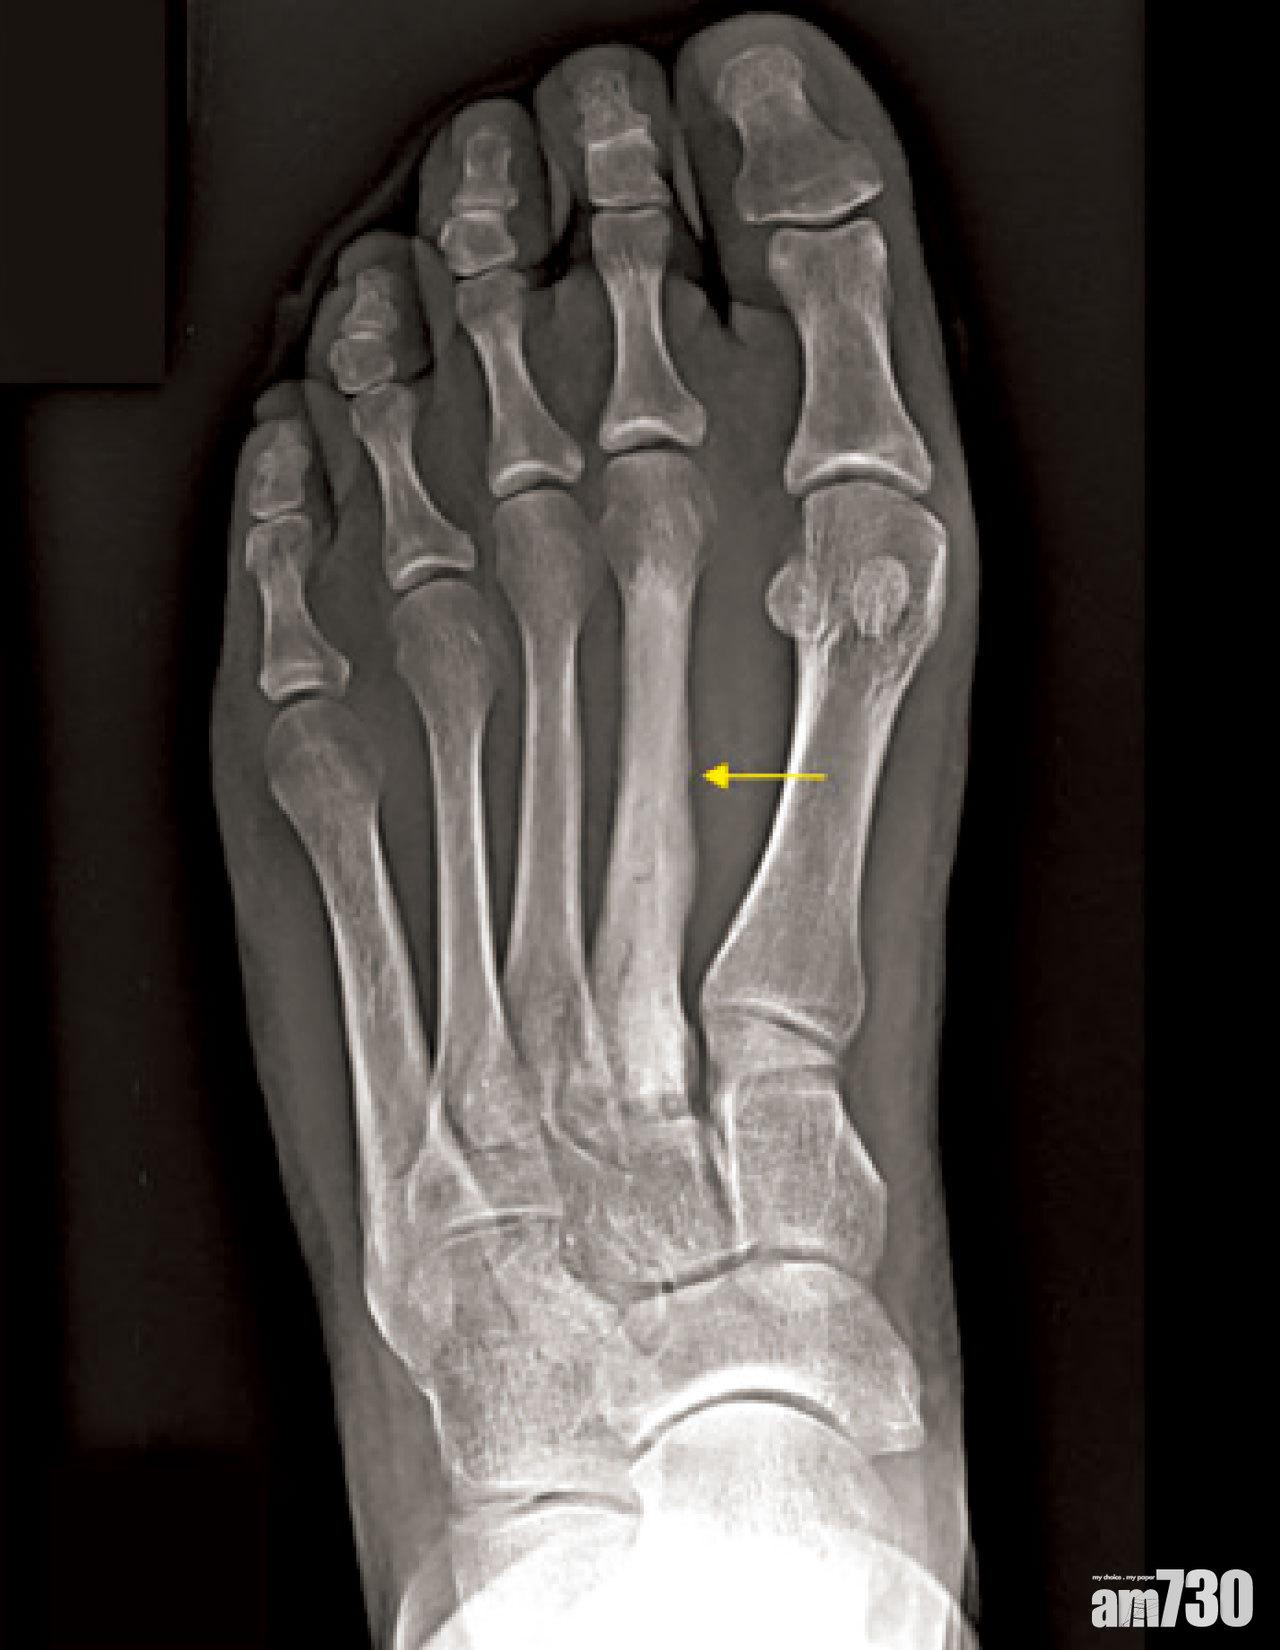

臨床上,疲勞性骨折多發於承受體重的骨幹,包括大腿骨、脛骨、腓骨及蹠骨。跑手的疲勞性骨折,常見於腳前掌的第二及第三蹠骨近腳趾頭位置,這是由於跑步時,須重複以腳掌落地的緣故;其次是見於大腿骨及小腿的脛骨,患者多為長跑運動員。沙惠良同時提醒市民,若穿上不慣常著的鞋履長時間走路,亦有可能導致小腿的腓骨出現疲勞性骨折。

疲勞性骨折常見於第二及第三蹠骨。

初期的疲勞性骨折,即使照X光亦難以察覺,不少個案是病情到了中至後期,再照X光時才發現骨骼曾因為反覆受傷而造成「生厚咗」的狀況。現時,醫生會先了解患者的生活和運動習慣,如懷疑患的是疲勞性骨折,就算是早期,也會安排患者接受骨掃描或磁力共振以加快確診,減低惡化風險。